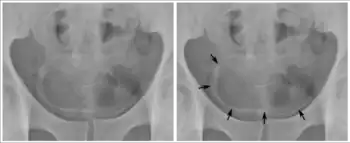

Cancer

Cancer of the bladder is known as bladder cancer. It is usually due to cancer of the urothelium, the cells that line the surface of the bladder. Bladder cancer is more common after the age of 40, and more common in men than women;[29] other risk factors include smoking and exposure to dyes such as aromatic amines and aldehydes.[29] When cancer is present, the most common symptom in an affected person is blood in the urine; a physical medical examination may be otherwise normal, except in late disease.[29] Bladder cancer is most often due to cancer of the cells lining the ureter, called transitional cell carcinoma, although it can more rarely occur as a squamous cell carcinoma if the type of cells lining the urethra have changed due to chronic inflammation, such as due to stones or schistosomiasis.[29]

Investigations performed usually include collecting a sample of urine for an inspection for malignant cells under a microscope, called cytology, as well as medical imaging by a CT urogram or ultrasound.[29] If a concerning lesion is seen, a flexible camera may be inserted into the bladder, called cystoscopy, in order to view the lesion and take a biopsy, and a CT scan will be performed of other body parts (a CT scan of the chest, abdomen and pelvis) to look for additional metastatic lesions.[29]

Treatment depends on the cancer's stage. Cancer present only in the bladder may be removed surgically via cystoscopy; an injection of the chemotherapeutic mitomycin C may be performed at the same time.[29] Cancers that are high grade may be treated with an injection of the BCG vaccine into the bladder wall, and may require surgical removal if it does not resolve.[29] Cancer that is invading through the bladder wall may be managed by complete surgical removal of the bladder (radical cystectomy), with the ureters diverted into a segment of part of ileum connected to a stoma bag on the skin.[29] Prognosis can vary markedly depending on the cancer's stage and grade, with a better prognosis associated with tumours found only in the bladder, that are low grade, that do not invade through the bladder wall, and that is papillary in visual appearance.[29]